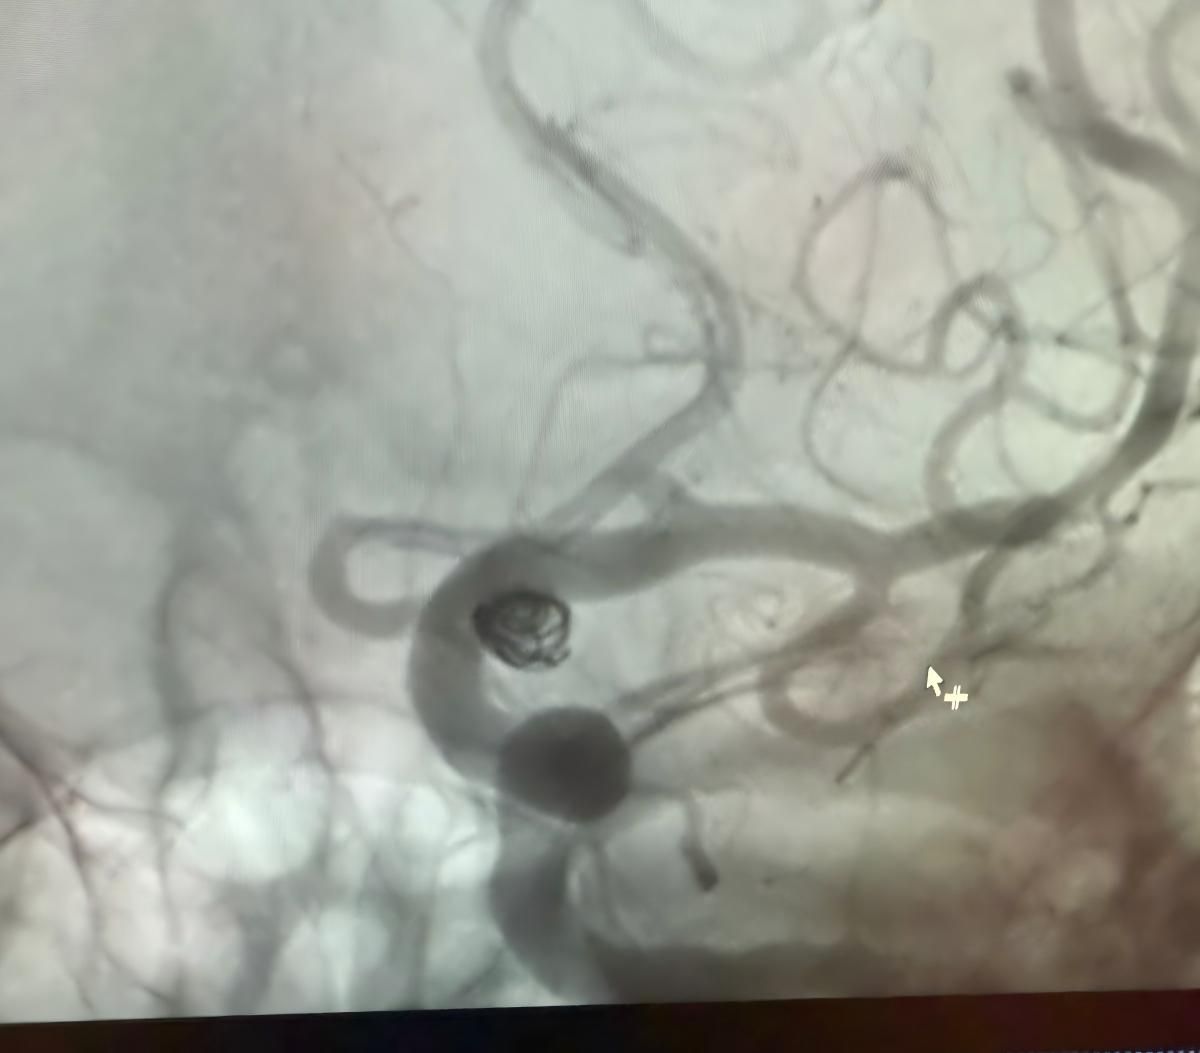

Wir freuen uns, ein kürzlich erfolgreiches Verfahren bei Clínica Alma Mater, Medel lín, zu teilen, das von Dr. Jorge Mutis durchgeführt wurde.

Die Behandlung nutzte die Nuva®Durchfluss-Diver ter (TJED-D 5.0-14), Perdenser®3D-Spule und Frepass®Mikro katheter (TJMC18 Plus) für ein posterior kommunizieren des Arterien aneurysma.

Dr. Mutis hob die hervorragende Sichtbarkeit des Geräts hervor und stellte fest, dass das Abrufen reibungslos verlief. Er zeigte sich sehr zufrieden mit dem Endergebnis.